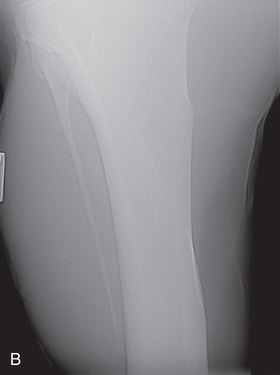

| Metacarpal/metatarsal cannon bone (M3) | Dorsoproximal-palmarodistal (DPr-PaDi) | Dorsopalmar (DP) |

| Lateromedial (LM) | Lateral (L) | |